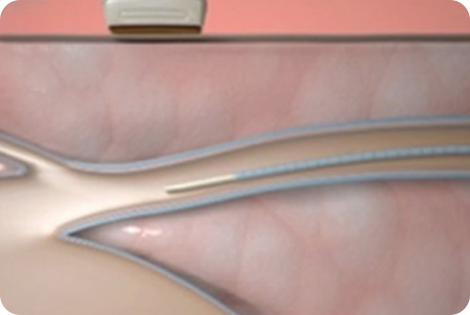

얇은 카테터(관)을

혈관에 삽입합니다

인체 친화적인

의료용 접합제를 주입합니다

해당부위를 압착합니다

혈관을 폐쇄하여 붙입니다